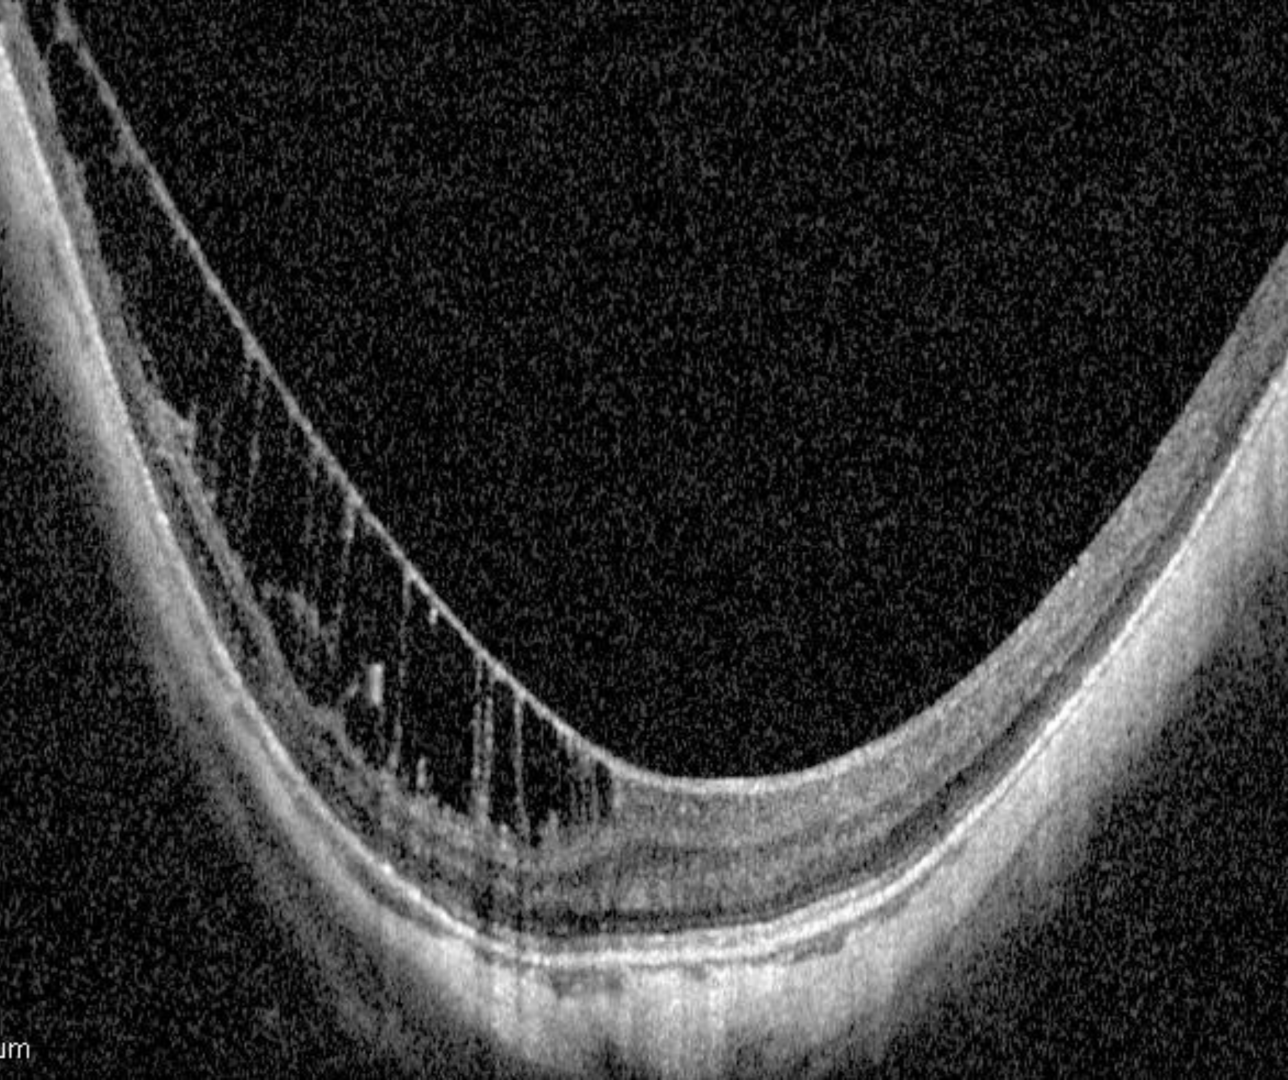

Inner limiting membrane (ILM) detachments are thought to result from staphyloma related traction in combination with the rigidity of the inner limiting membrane. They are often associated with an underlying retinoschisis in high myopes and may progress over time.

On OCT the inner-most retinal layer (the ILM) detaches from the rest of the retinal layers. There is often residual tissue that bridges the membrane to the retinal tissue and this can help differentiate an ILM detachment from an ERM. The bridges may be lost however with time, increased traction and retinal atrophy.